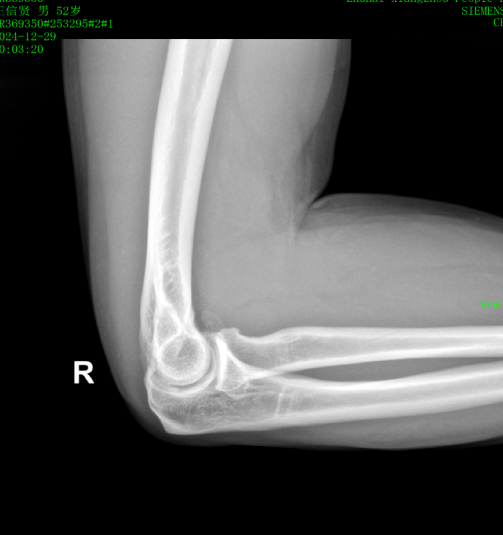

近日,一位52岁的男性患者,因右肘疼痛伴活动受限2周余来pilipili 就诊。经检查,确诊为肘关节骨性关节炎伴游离体。患者于入院第二天在气管插管麻醉下行右肘关节镜探查+滑膜切除+游离体取出术。术后症状明显缓解,疼痛减轻,关节活动范围改善,现已成功出院。

患者鹰嘴骨质增生;前侧关节腔游离体形成

术后CT、DR提示游离体取出